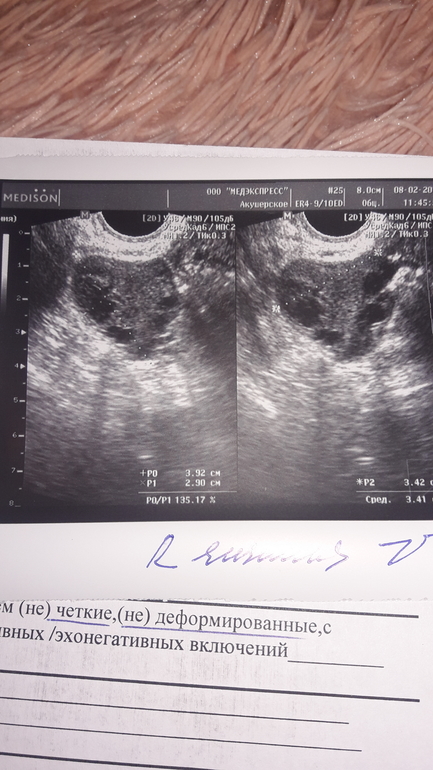

Девушки всем привет. Подскажите пожалуйста. У меня 28 дц. Мерию БТ каждый цикл. По ощущениям овуляция была. весь 2 цикл ТТ от 37-37.3( постоянно). БТ по утрам ровно 37. Вчера съездила на узи( в первый раз была именно в этой клинике) Узист мне сказала, что увеличен ПЯ. Но это не киста и не воспаление.ЖТ говорит нету. Мог ли Узист ошибиться? Как по фото мне кажется что большой не ровной формы кружочек и есть жт. Объем ПЯ 20мл. Говорит может там инфекция какая то. Доверия она мне не внушила.

На фото у вас фолликулы, жт я тоже не вижу

Жёлтого тела я там не увидела... Оно обычно как кружочек или овал

По фото у вас там фолликулы. В ЖТ есть кровоток, значит узистка не увидела это. Сдайте мазок, чтобы исключить воспаление.